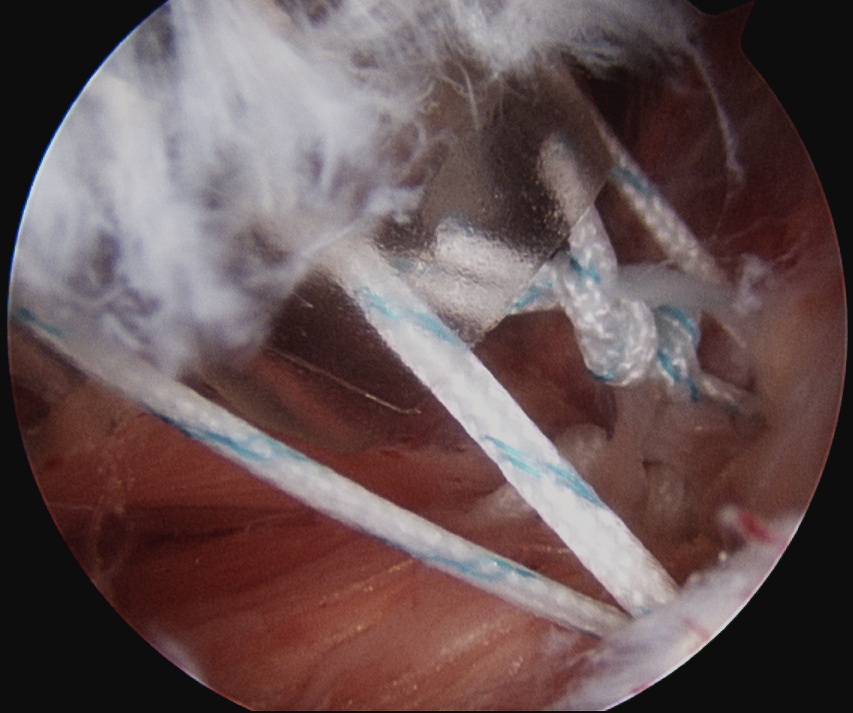

Tying knots under direct vision in the subdeltoid space using double pulley technique